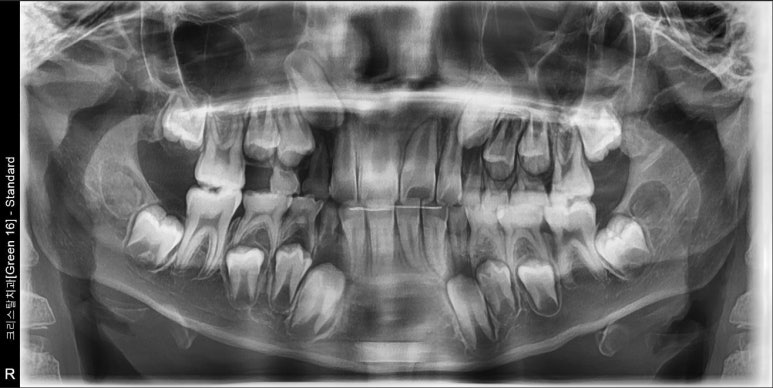

#15의 맹출 공간이 부족하여 내원한 9세 남아 입니다. 빠르게 1차교정을 마무리 했습니다.

1차교정은 6-9개월 안에 cc만 해결하고 가급적 빨리 마무리하는 것이 최선입니다.

어치피 나머지 영구치가 맹출하고 나면 또 삐뚠 치아들이 나타나는 경우가 대부분이라

5-6학년 때 2차교정이 필요한 경우가 대부분입니다. 그래서 1차라는 표현이 들어가 있는 것이죠^^

1차교정이 길어지면 아이도 지치고, 특히 부모도 지치게 되는데 나중에 또 2차교정을 하려고 하면

진짜 본 게임에서 모두 지쳐서 진행이 쉽지 않아지기 때문입니다.